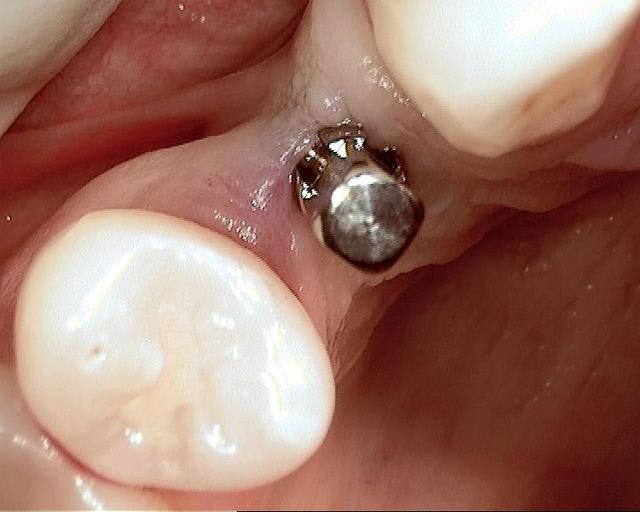

Photos d'un cas d'extraction implantation immédiate, stabilité primaire (de mémoire) assez élevée.. 60/70 N ..démontage du gingiva clips et du shuttle, pilier serré 40N, couronne procera

Merci pour le cas, bien fait. Belle présentation photo.

Le contour gingival est net, belle guérison, c'est à combien de semaine ?

Je vois un peu de ciment sur la radio finale, attention, c'est pas bien pour les tissus.

Oui je sais pour le ciment... j'utilise d'ailleur ce cas et cette radio dans une présentation pour mettre en garde sur le risque au moment du scellement de voir du ciment fuser sous la limite prothétique vers la col de l'implant..galère à éliminer...Personnellement je préfere plutot utiliser des piliers à usiner (maintenant disponibles voir shop online pour photos) au lieu des strandarts meme si il y a deux hauteurs/col implantaire en 1 et 3mm aujourd,hui disponibles..A l'époque de ce cas il n'y avait que les 1 mm et la limite est un "poil" trop profonde.

La pose de la couron nec'est faite 8 semaines apres l'extraction implantation immédiate, la particularité de ce systeme permet de ne pas démonter le shuttle ni la gingivaclip pour l'empreinte..je pense que ca aide bien à la qualité gingivale...radio controle ci jointe